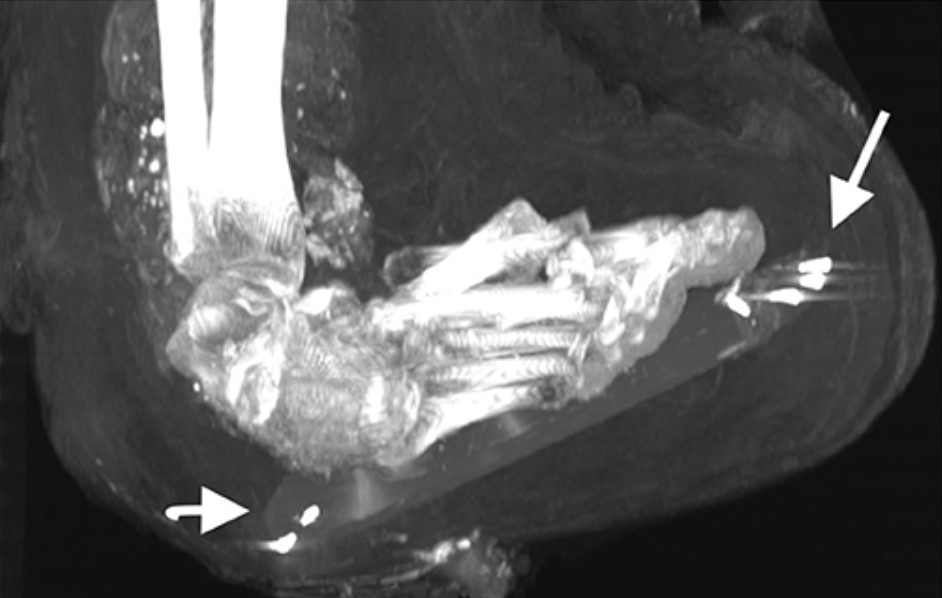

Hai ngón tay bị thiếu của bàn tay trái được đặt bên trong khoang cơ thể (nhìn theo hướng mũi tên dài màu đen). (Ảnh: Đăng dưới sự cho phép của Sahar N. Saleem và Zahi Hawass)

Bàn chân phải của xác ướp [pharaoh] Amenhotep I với những chiếc đinh có khả năng được ghim vào để cố định vị trí của mảng gỗ với các lớp bọc xung quanh. (Ảnh: Đăng dưới sự cho phép của Sahar N. Saleem và Zahi Hawass)

Những người ướp xác sẽ đọc những câu thần chú và bọc những thứ này lại như một sự bảo hộ cho người đã khuất. Các vật dụng khác bao gồm một chuỗi gồm 34 hạt bằng vàng được đặt ở phần thắt lưng của xác ướp, ghim vào bằng xương hoặc ngà voi, và đinh kim loại được sử dụng trong quá trình bọc xác và để giữ cố định các chi.

Bằng chứng của những kẻ trộm mộ cũng đã được hiển hiện. Cánh tay trái đã bị trật khớp và rồi được bọc lại dọc theo cơ thể xác ướp. Tuy nhiên, cánh tay phải của xác ướp đã cong lại ở phần khuỷu tay và phần cẳng tay đặt lên bụng, cho thấy rằng cả hai cánh tay có thể đã từng được bắt chéo theo một dạng thức tương tự. Hai ngón tay của bàn tay trái cũng bị tháo rời, có thể là do những kẻ trộm mộ, và nằm bên trong một lỗ hổng lớn của thành khoang bụng. Đáng chú ý hơn, cổ của xác ướp đã bị cắt đứt, phần đầu lìa ra và được gắn lại bằng một dải vải lanh được xử lý qua nhựa cây với một tấm bùa bảo hộ được đặt bên dưới.